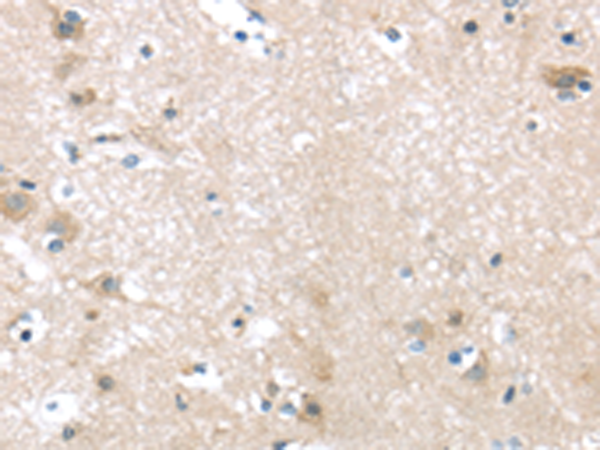

IHC positive control:

Human brain and Human liver cancer

IHC Recommend dilution:

10-50